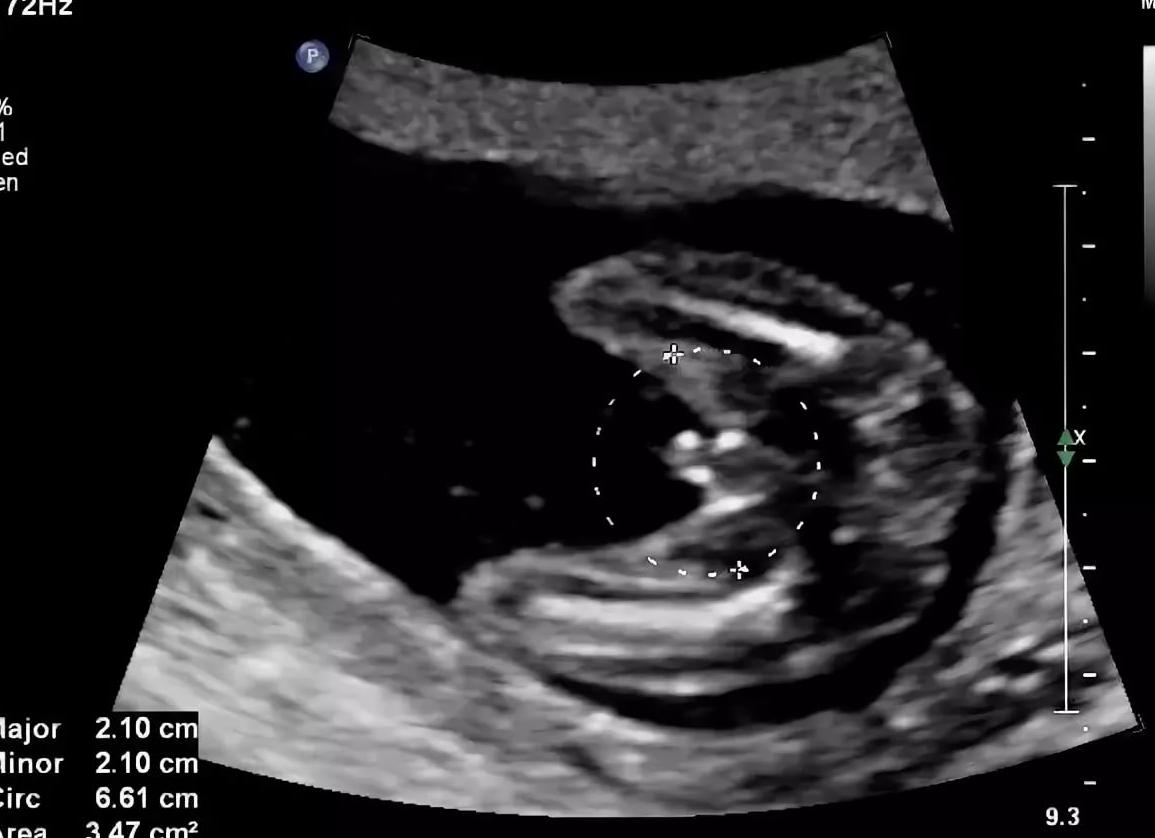

в общем у меня срок 5 акушерских недель и 3-4 дня или 3 недели и 3,4 дня дня от зачатия. по узи плодное яйцо неправилтьной формы 9*4,5 мм. врач сказала, что это очень мало, должно 17 мм. см. не исключила неразвивающуюся беременность, сказала через неделю повтор узи. в интернете таблицы, в идеале должно быть 18 мм на этом сроке и эмбрион 3 мм, но по одной таблице нашла, что 9 мм. соответствует сроку 5 недель и 5 дней. хгч у нас делают раз в неделю, завтра поеду сдам, но в динамике посмотреть не получится. у кого-нибудь было такое? может ли плодное яйцо отставать в развитии, но нормально развиваться?